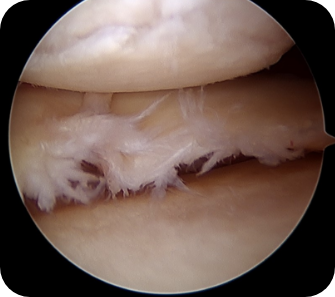

• ▲ 무릎 연골판 이식술 전

• ▲ 무릎 연골판 이식술 후

• 3) 관절경하 연골판 이식술

반월상 연골판의 심한 파열이나 원판형 연골판의 손상 등으로 인해 남아있는 연골판이 거의 없는 경우, 새로운 연골판을 이식해주는 방법입니다. 다른 사람의 기증받은 연골판을 이식하는 것으로 무릎관절 및 연골판의 크기가 비슷한 것을 처리하여 부작용이 없게 만든 후 사용하게 됩니다.

수술방법

관절내시경을 이용하여 무릎 안을 보면서 약 3~4cm 정도 절개하여 경골고평부에 구멍을 뚫고 뼈가 붙어있는 연골판을 구멍에 맞추어 다듬은 다음 넣어 고정합니다.

수술장점

새로운 연골판을 뼈와 같이 이식하기 때문에 가장 안정적인 유합을 얻을 수 있으며, 연골판을 살릴 수 없는 상태에서 가능한 유일한 방법입니다.